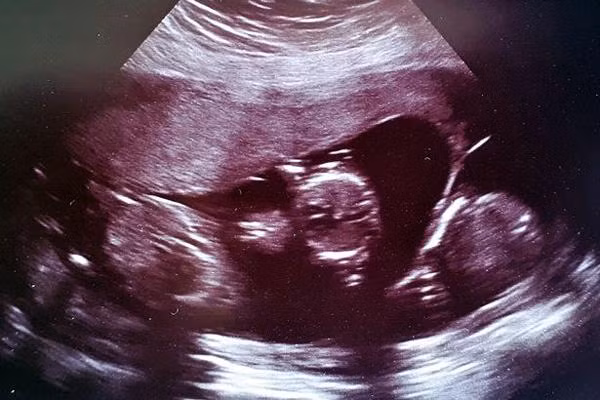

Ngày hôm sau, Stacey đến bệnh viện siêu âm và chính bác sĩ cũng không tin vào mắt mình khi phát hiện hai nhịp tim thai trong tử cung của cô và cả hai đều trong tình trạng ổn định.

"Các bác sĩ đã không phát hiện ra cặp song sinh khi siêu âm trước đó và cả khi phẫu thuật bỏ thai ngoài tử cung. Chúng vẫn phát triển ở đó sau mọi chuyện. Thật kỳ diệu", Stacey chia sẻ.D

Điều kỳ diệu hơn nữa đến vào 4 tuần sau đó, khi bác sĩ siêu âm thai 12 tuần và phát hiện một trong hai phôi đã tách đôi. Tức là Stacey mang thai 3 chứ không còn là thai đôi nữa.